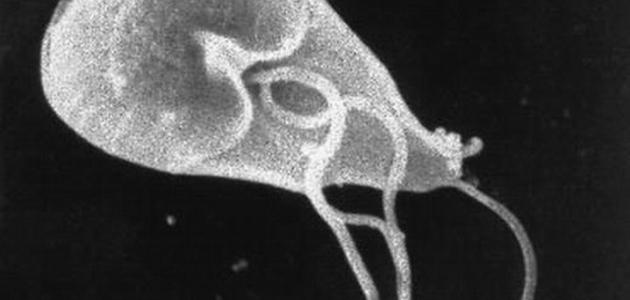

ما هي طفيليات الجيارديا وما أعراض الإصابة بها

عمون- تُعرّف الطفيليّات (بالإنجليزية: Parasites) بأنّها كائنات حية دقيقة تعيش على كائن حي آخر. تُعتبر الجيارديا (بالإنجليزية: Giardia) طفيليّاتٍ مجهرية توجد على الأماكن مثل التربة، والطعام، والماء الملوّث ببراز الحيوان أو الإنسان المصاب بها. تمتاز هذه الطفيليات بغلاف خارجي يمكّنها من البقاء لفترات طويلة خارج أجساد الكائنات الحية، وقد تصل هذه الفترات إلى أسابيع أو حتى شهور. هذا الغلاف يجعلها مقاومة للمعقّمات التي تحتوي على الكلور.

الجيارديا تُسبّب داء يُعرف بـ "داء الجيارديات" (Giardiasis). عند إصابة الإنسان أو الحيوان بها، تعيش في أمعائهم وتنتقل إلى برازهم. يُشير مراكز مكافحة الأمراض والوقاية إلى أن حوالي 16,000 شخص يُصابون بهذه العدوى سنوياً في الولايات المتحدة. وهي شائعة أيضًا في العديد من مناطق العالم، خاصة في الدول النامية، حيث يكون ما يقرب من 20-30% من السكان عرضة للإصابة بها مرة على الأقل في حياتهم.